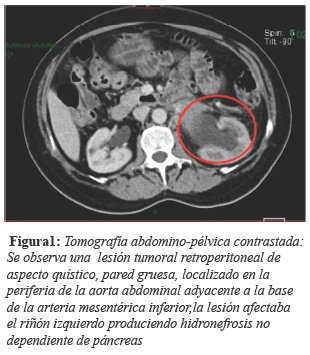

Presentamos el caso de una mujer de 55 años de edad, sin antecedentes clínico-patológicos de importancia, quien inició su padecimiento hace 5 meses con dolor en región dorsolumbar izquierda de tipo punzante, irradiado en hemicinturón ipsilateral con intensidad 8/10, acompañado de alzas térmicas, náuseas y vómitos, ameritando múltiples tratamientos médicos fallidos a base de analgésicos y antibióticos, los últimos 5 meses por probables infecciones de vías urinarias, colitis y gastritis con mejoría parcial de los síntomas, motivo por lo que se realizan estudios de gabinete documentando por tomografía abdominopélvica simple y contrastada donde se observa una lesión tumoral retroperitoneal, de aspecto quístico,de pared gruesa, localizado en la periferia de la aorta abdominal, que afecta el riñón izquierdo (figura 1) produciendo hidronefrosis moderada, no dependiente del páncreas. Los exámenes paraclínicos están dentro de parámetros normales y los marcadores tumorales para cáncer de páncreas fueron negativos. Se le realiza laparotomía exploratoria, nefrectomía radical izquierda, tumorectomía retroperitoneal y resección de un fragmento de aorta abdominal, con hallazgos durante la cirugía de tumor sólido adherido a planos profundos de 7 cm de diámetro con infiltración a riñón izquierdo y aorta, con reacción desmoplásica severa.